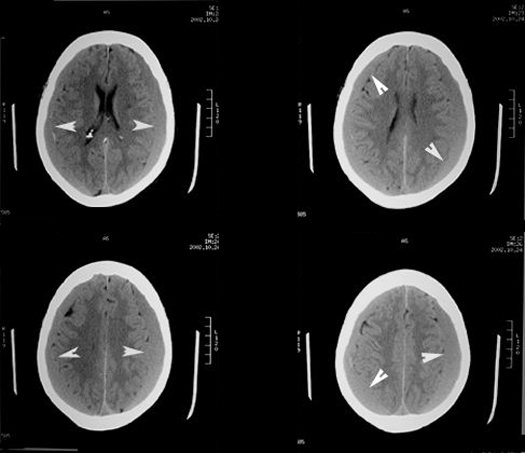

Bilateral subacute Subdural Hematoma

Case 4:

Imaging findings:

Figure 4: Pre-contrast axial CT

- There are bilateral subdurals (arrow heads) isodense with the brain due to the gradual loss of density of blood.

- On close examination you see that the sulcal markings do not reach the surface of the skull, due to the intervening subdural collection.

- Arrowheads point to subdurals separating the brain surface from the skull.

- There is no midline shift due to bilaterality of subdurals.